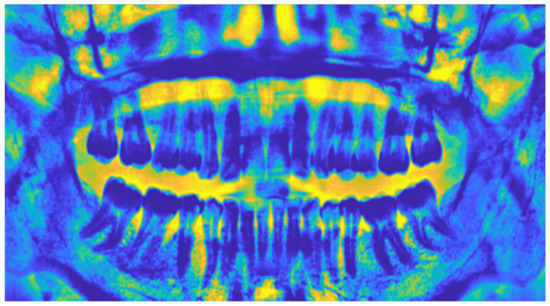

2.1.4. Adaptive Histogram Equalization